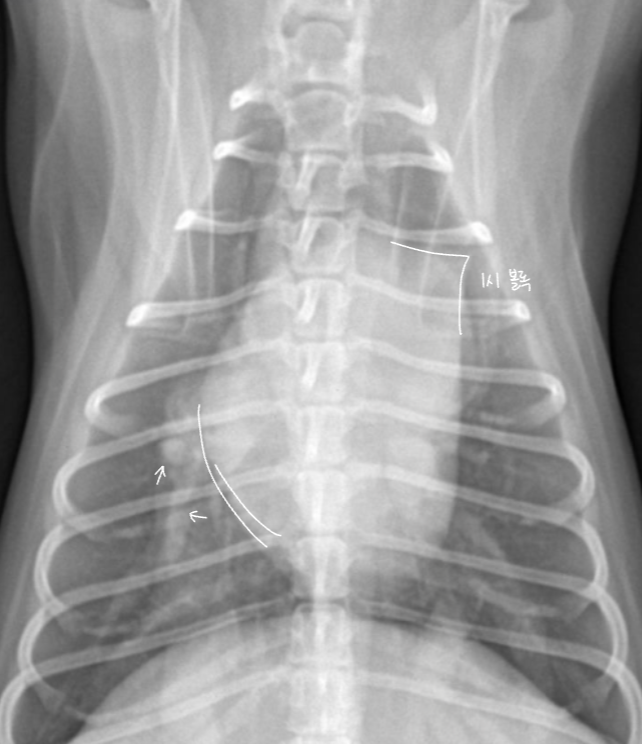

| LA enlargement |

| - wing sign, backpack sign - bow-legged cowboy sign - double wall sign HCM์์ ์ ๊ด์ฐฐ๋๋ค. |

![]() ![]() |